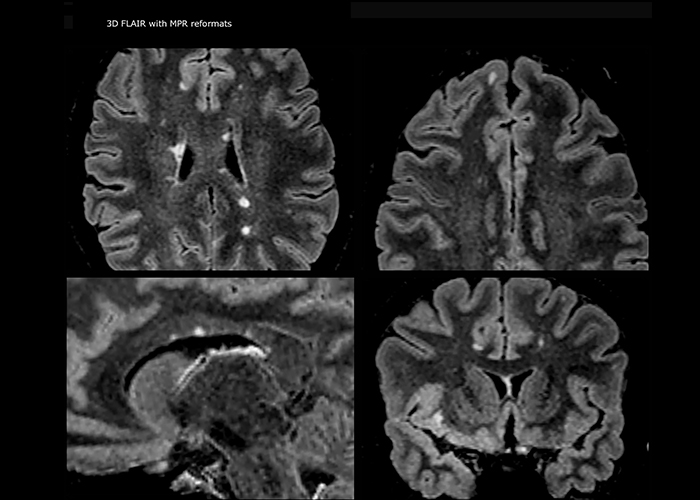

When multiple sclerosis (MS) is suspected, clinicians need a diagnosis early on, so treatment can begin as soon as possible. “A challenge for imaging is that MS lesions in the brain and spine may be very small,” says Dr. Savatovsky. “We need precise imaging to tell exactly where the lesion is, so we need high quality, very high resolution images, preferably in 3D[1]. We need to know if a high T2 signal intensity is suggestive of MS or just aspecific. And we want to visualize active lesions very well.”

“Ingenia 3.0T provides us very good image quality with high SNR, even if we push the resolution. For example, in FLAIR images we may have an isotropic resolution of 0.9 mm. Ingenia allows us to use 3D T1 TSE with BrainView, which has a better sensitivity than 2D spin echo imaging[2] and 3D gradient echo imaging. Ingenia also provides highly reproducible exams, which is important in MS imaging so that follow-up exams at different time points are done the same way.”

For MS imaging in the brain, Dr. Savatovsky uses 3D FLAIR as the basic sequence to visualize the lesions and assess the situation and lesion load. “We count the lesions in each location to determine if the criteria of the disease are fulfilled. We use a T2-weighted sequence because our neurologists are used to it. We compare the lesion load on FLAIR with a 3D T1 post-contrast sequence to help us determine whether lesions are old or new. We typically administer the contrast before the patient enters the machine because it shortens the examination time and allows to visualize active lesions that tend to be more visible after several minutes. When a differential diagnosis is difficult, we add sequences such as susceptibility imaging, because some focal MS lesions have a small vein in the center[3].”